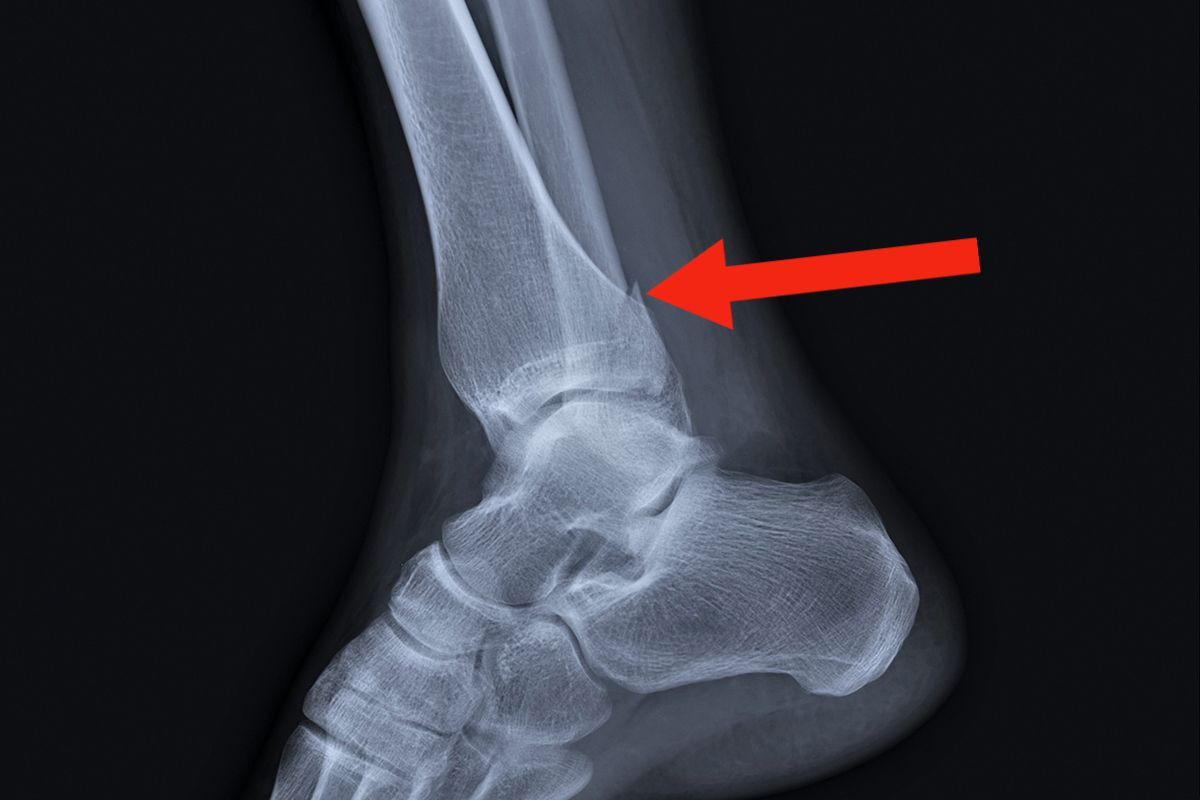

- Исследовать характер травмы голеностопного сустава позволяет рентгенологическое обследование. В процессе диагностики оценивается состояние целостности кости, смещение фрагментов.